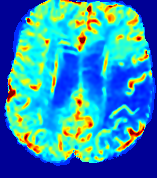

LesionRefer to captionRefer to captionRefer to captionRefer to captionRefer to captionRefer to caption𝐕rgbsubscript𝐕𝑟𝑔𝑏{\bf{V}}_{rgb}Refer to captionRefer to captionRefer to captionRefer to captionRefer to captionRefer to caption𝐕2subscriptnorm𝐕2{\|\bf{V}}\|_{2}Refer to captionRefer to captionRefer to captionRefer to captionRefer to captionRefer to captionRefer to caption3.53.53.52.82.82.82.12.12.11.41.41.40.70.70.70.00.00.0(mm/s)𝑚𝑚𝑠(mm/s)D𝐷DRefer to captionRefer to captionRefer to captionRefer to captionRefer to captionRefer to captionRefer to caption0.0200.0200.0200.0160.0160.0160.0120.0120.0120.0080.0080.0080.0040.0040.0040.0000.0000.000(mm2/s)𝑚superscript𝑚2𝑠(mm^{2}/s)Slice #1Slice #2Slice #3Slice #4Slice #5Slice #6

Figure 3: PIANO feature maps for one stroke patient, where the lesion is located in the left hemisphere. Top row: segmented stroke lesion region (white) on different slices, obtained from ISLES 2017. The corresponding slices for the PIANO feature maps are shown in the following rows.

For a better insight into an estimated velocity field 𝐕𝐕{\bf{V}} and diffusion field 𝐃𝐃{\bf{D}}, we compute the following maps: (1) 𝐕rgbsubscript𝐕𝑟𝑔𝑏{\bf{V}}_{rgb}: Color-coded orientation map of 𝐕=(Vx,Vy,Vz)T𝐕superscriptsuperscript𝑉𝑥superscript𝑉𝑦superscript𝑉𝑧𝑇{\bf{V}}=(V^{x},V^{y},V^{z})^{T}, obtained by normalizing 𝐕𝐕{\bf{V}} to unit length and mapping its 3 components to red, green, blue respectively; (2) 𝐕2subscriptnorm𝐕2\|{\bf{V}}\|_{2}: 222 norm of 𝐕𝐕{\bf{V}}; (3) D𝐷D: scalar field in Eq. 5.

Fig. 3 and Fig. 4 show the PIANO feature maps estimated from two ISLES 2017 patients: all are highly consistent with the lesion in both cases. Details of the blood flow trajectories are revealed in 𝐕rgbsubscript𝐕𝑟𝑔𝑏{\bf{V}}_{rgb} by the ridged patterns and the sharp changes of colors in the unaffected (right) hemisphere, while the flat patterns appearing within the lesion provide little directional information about the velocity and indicate low velocity magnitudes. Velocity magnitudes are more directly visualized via 𝐕2subscriptnorm𝐕2\|{\bf{V}}\|_{2}, from which one can easily locate the lesion where 𝐕2subscriptnorm𝐕2\|{\bf{V}}\|_{2} is low. D𝐷D also indicates lower diffusion values in the lesion, though with less contrast potentially due to the fact that it captures the accumulated effect of CA diffusion at the voxel-level.